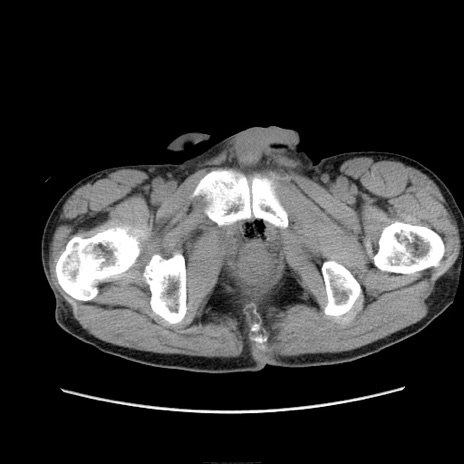

症例11(横断像)

【症例】 60歳代男性

【主訴】 下腹部痛

【現病歴】 本日夜中より下腹部痛の症状認め、受診。

【既往歴】 膀胱癌(膀胱全摘+尿管皮膚瘻術) 、胃癌術後

【身体所見】 BT 35.3℃、PR 58/min、BP 136/98mHg、腹部平坦、軟、腸蠕動音±、ストマ留置あり、左上腹部~正中部に圧痛あり、反跳痛なし。

【データ】WBC 5100、CRP0.01